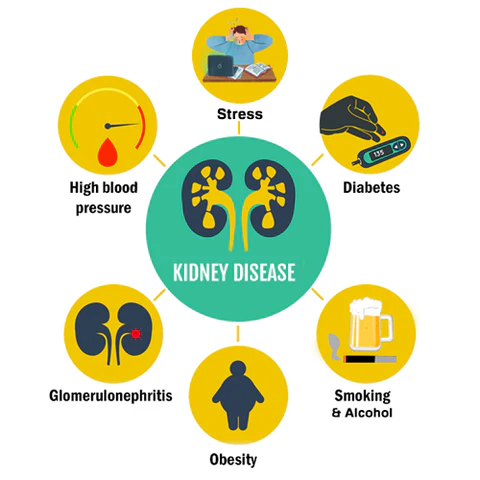

Factors affecting kidney health